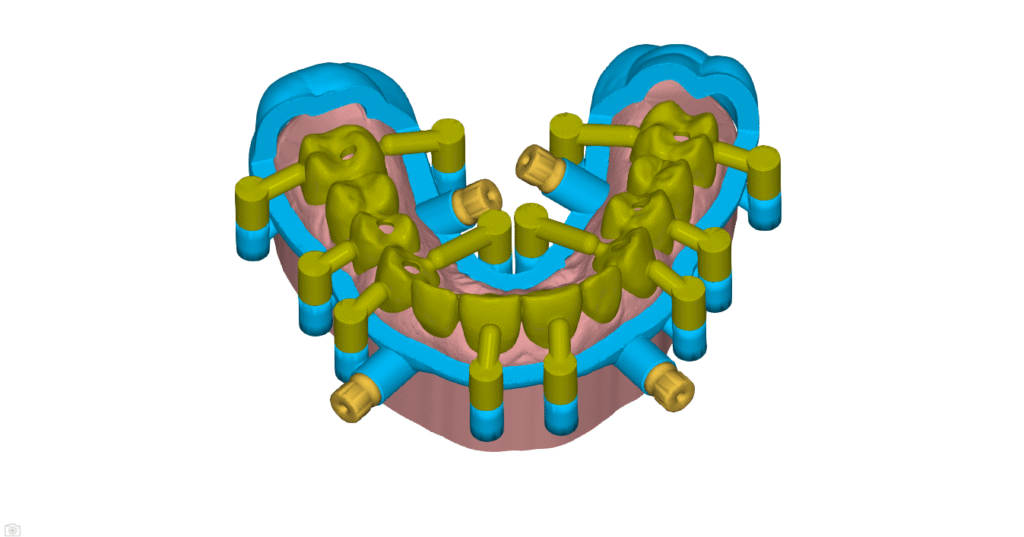

Implant Planning & Surgical Guides

Guided surgery is fast becoming the standard of care in the modern world.

Allow us to perfectly plan your implant case, based on years of experience from single unit to full arch cases.

We use NemoScan Implant Planning Software from Nemotec- SPAIN, a Henry Schein Company. NemoScan is the worlds most advanced implant planning software that gives us abilities that no other software on the market gives.

Stackable Guide

These guides are used for full-arch FP1 and FP3 cases and can be gingiva-supported or bone-supported. These cases are complex and typically performed by Dental Specialists. We use JB Dental Lab in the USA for the design and manufacture of the final prosthesis, but we can manufacture the temporary prosthesis locally. Feel free to use your preferred lab.